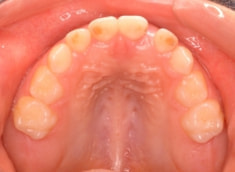

治療前